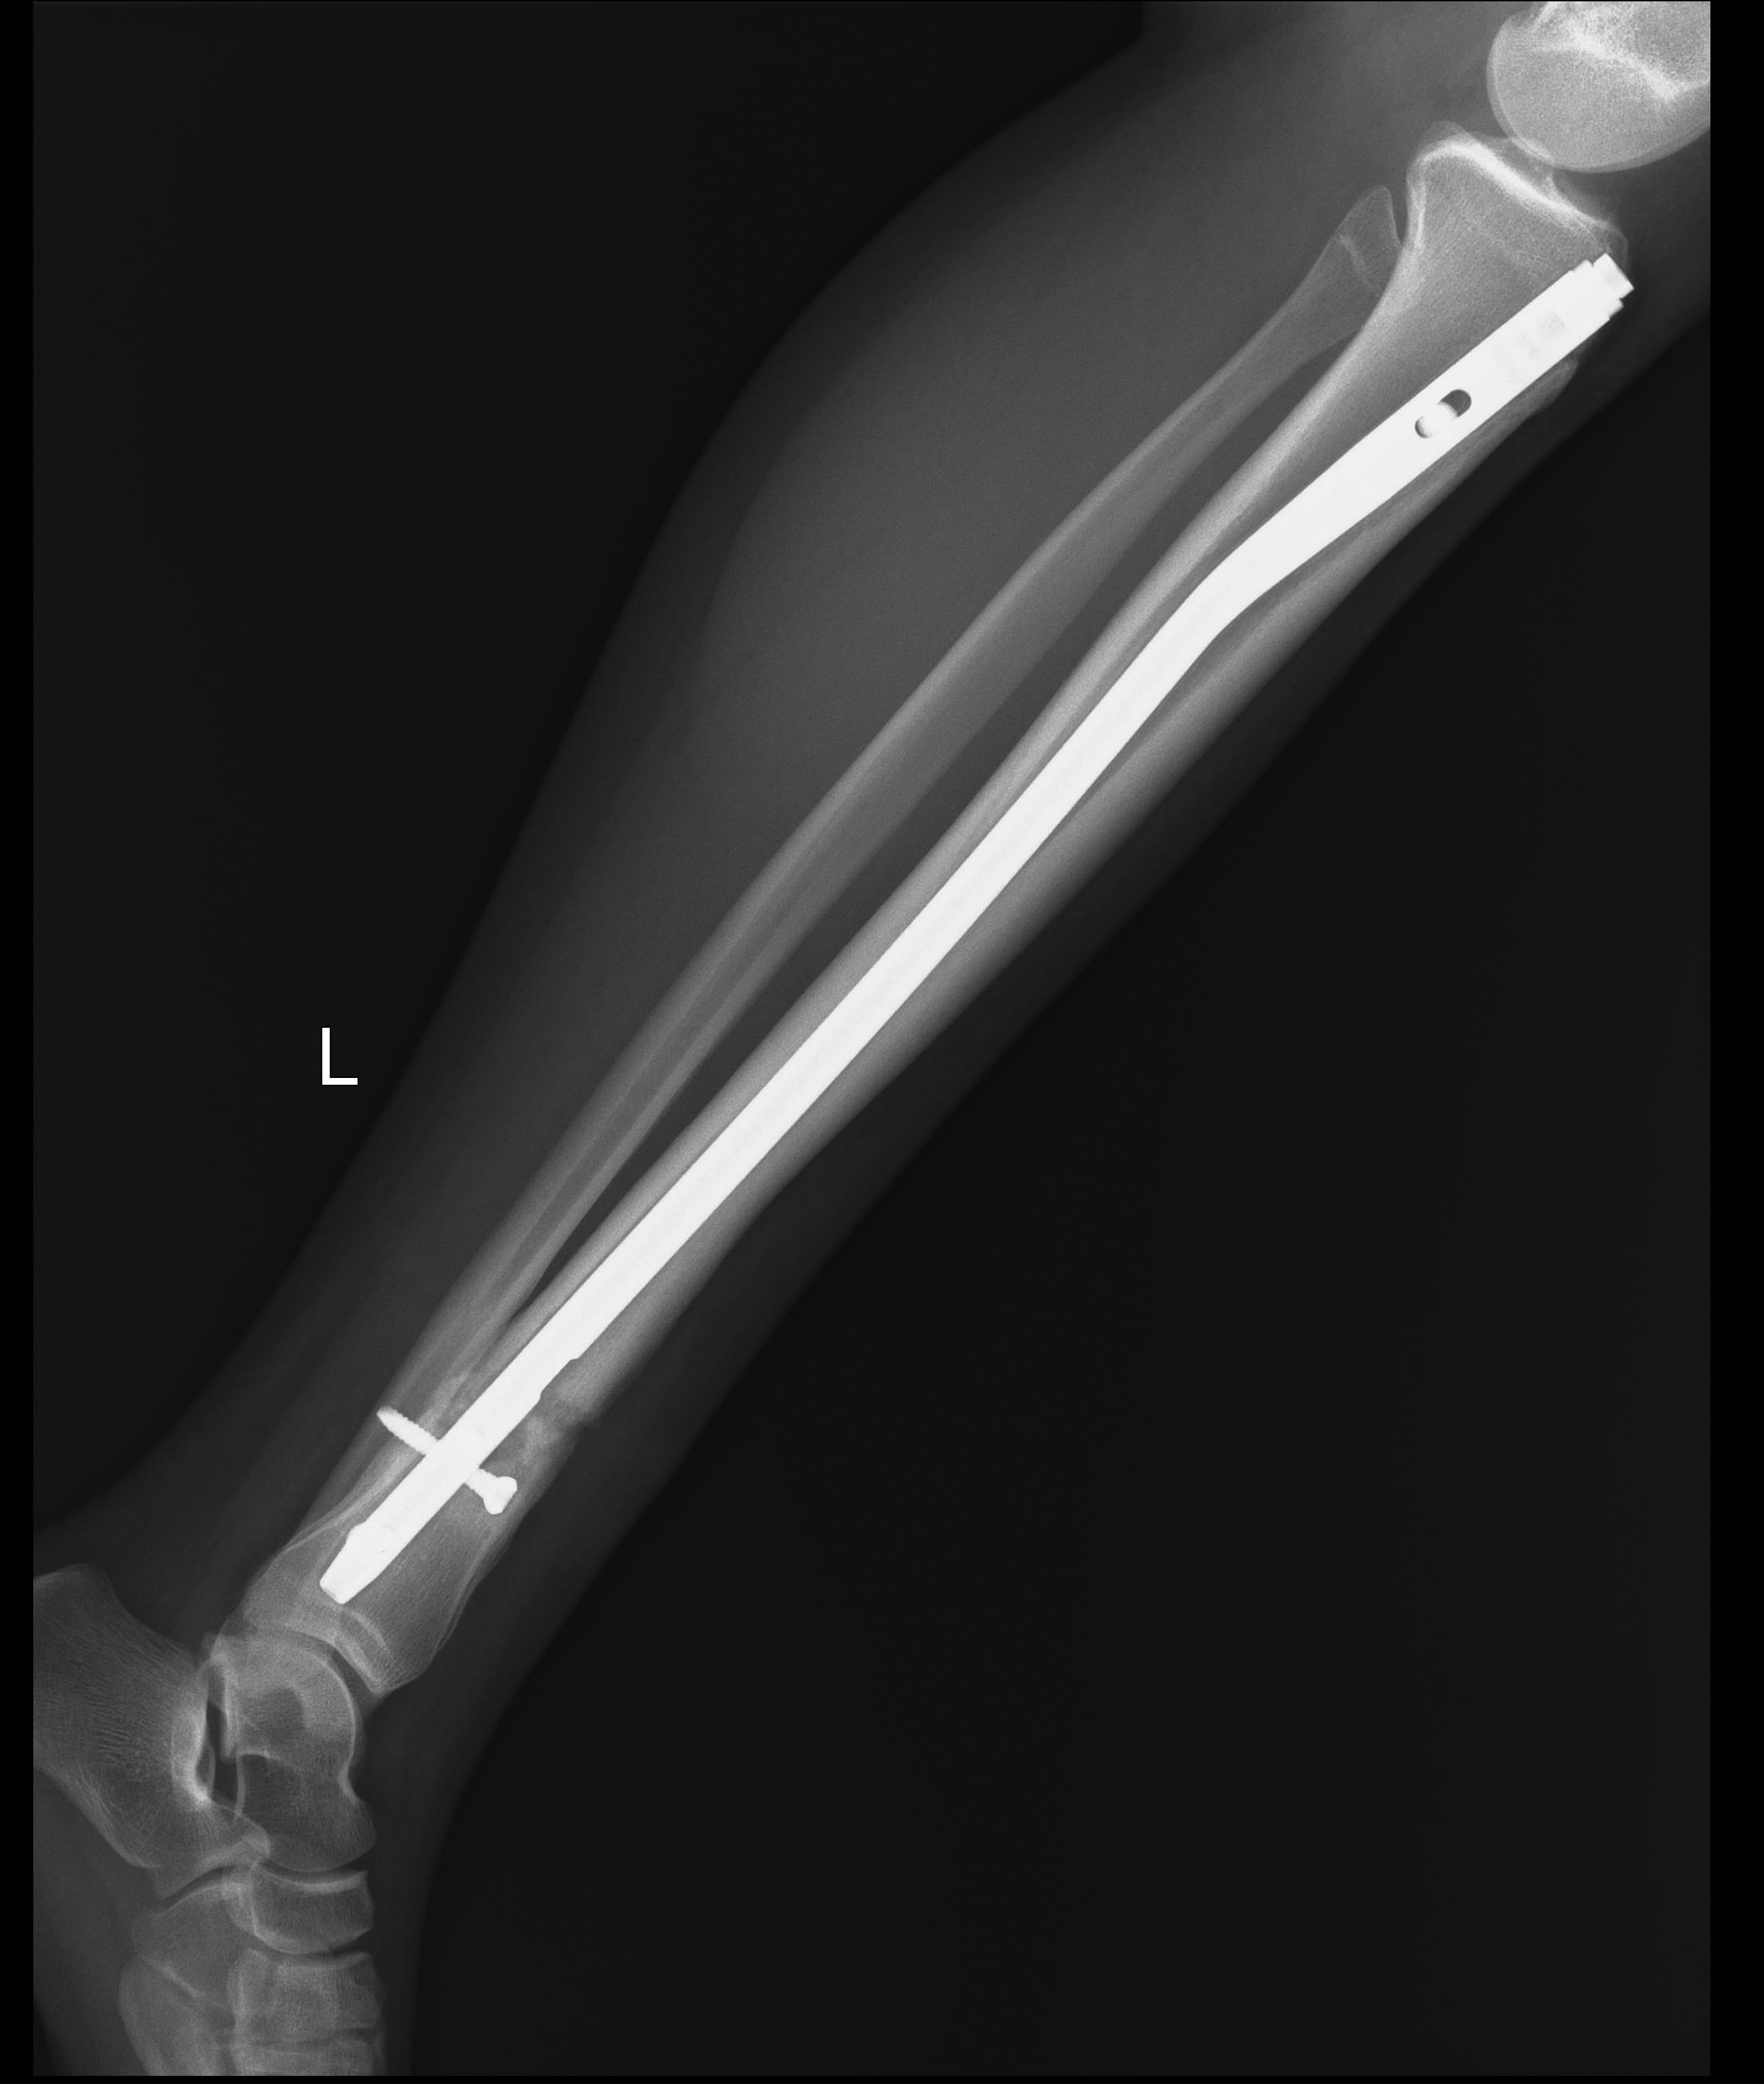

[Ortho] Несращение голени

Имя     : Через 8 месяцев1.jpg

Имя     : Через 8 месяцев2.jpg